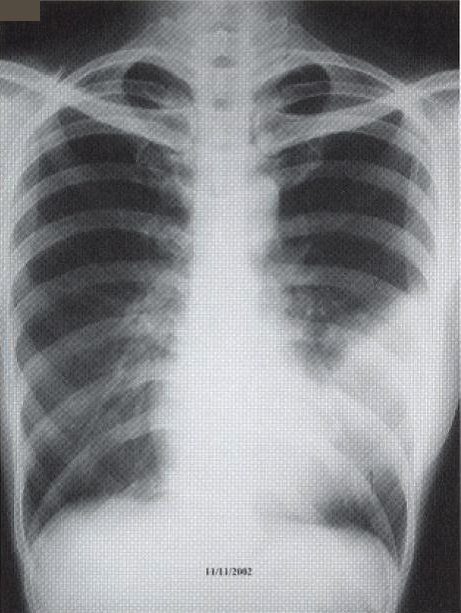

A 41-year old secretary was found having a left mid zone opacity on a routine CXR taken as part of her annual medical check-up (fig. la). This radiographic abnormality persisted after she was given a course of Azithromycin by her family physician (fig. 1b). She was a lifelong non-smoker with a past history of hyperthyroidism treated with drugs for 18 months in 1985-86 and had been euthyroid since. Two months prior to her medical check-up, she had a flu-like illness with cough and a sore throat that lasted for about a fortnight. She had been asymptomatic since apart from a slight cough occasionally. She denied any fever, weight loss, night sweat or pruritus. There was no history of taking any long-term medication or exposure to chemicals or animal pets. Clinical examination was normal and in particular, she was afebrile and not in respiratory distress. SaO2was 98% at rest whilst she was breathing room air and spirometry was normal.

Fig. 1: CXR taken at presentation (a) and 17 days later (b). Left mid zone opacity remained unchanged despite a course of Azithromycin Blood tests revealed normal CBP, ESR & routine biochemistry. Antibodies for HIV 1 & 2 were negative. Thyroid function was normal but thyroid peroxidase antibody was elevated at 81.7 IV/ml (normal <12). CT thorax showed an area of segmental consolidation in the lingular segment of left upper lobe (fig. 2a), with no abnormality detected in other parts of the lungs, mediastinum or body structures. Bronchoscopy revealed nothing abnormal and bronchial washings grew alpha streptococcus but were negative for AFB smear, M tuberculosis DNA or malignant cells. She developed a cough after the bronchoscopy and responded to a course of levofloxacin.